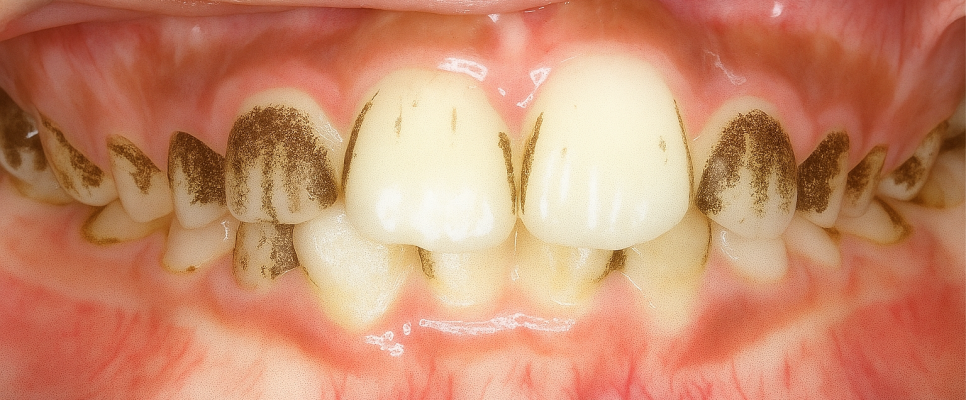

구강 내 모습을 보았을 때

전치부의 자연치가 정상적인 이와 달리

색과 형태가 좋지 않습니다.

이는 전형적인 법랑질 저형성증으로,

14번, 24번의 광범위한 결손에는

라미네이트 진료가 적용될 수 있으며,

33번, 43번의 국소적 결손에는

레진 수복 치료가 고려될 수 있습니다.